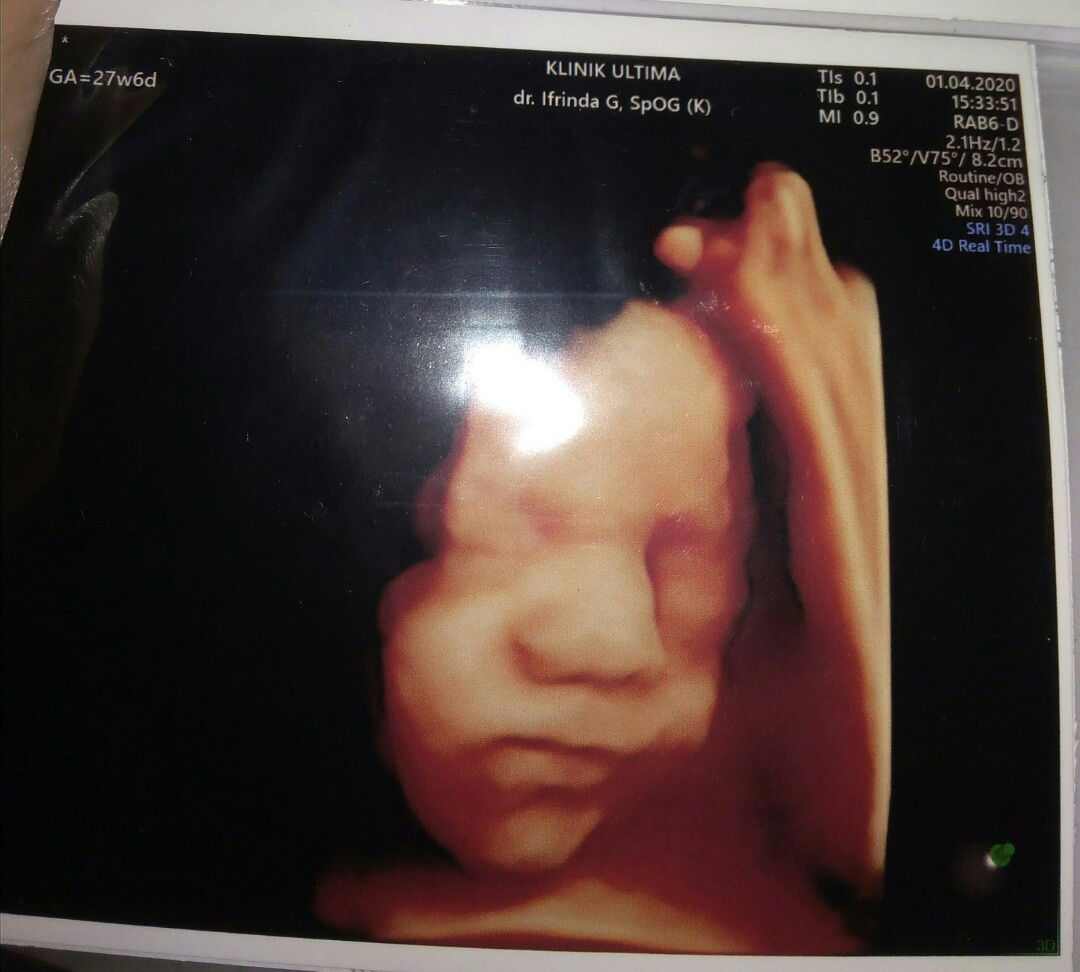

melintang

Bun USG kemarin kata Bu dokter nya si utun melintang. Jadi panik nih padahal udah ikhtiar sujud tiap bangun tidur sama kalo mau tidur .ini usia kandungan 28 week ?